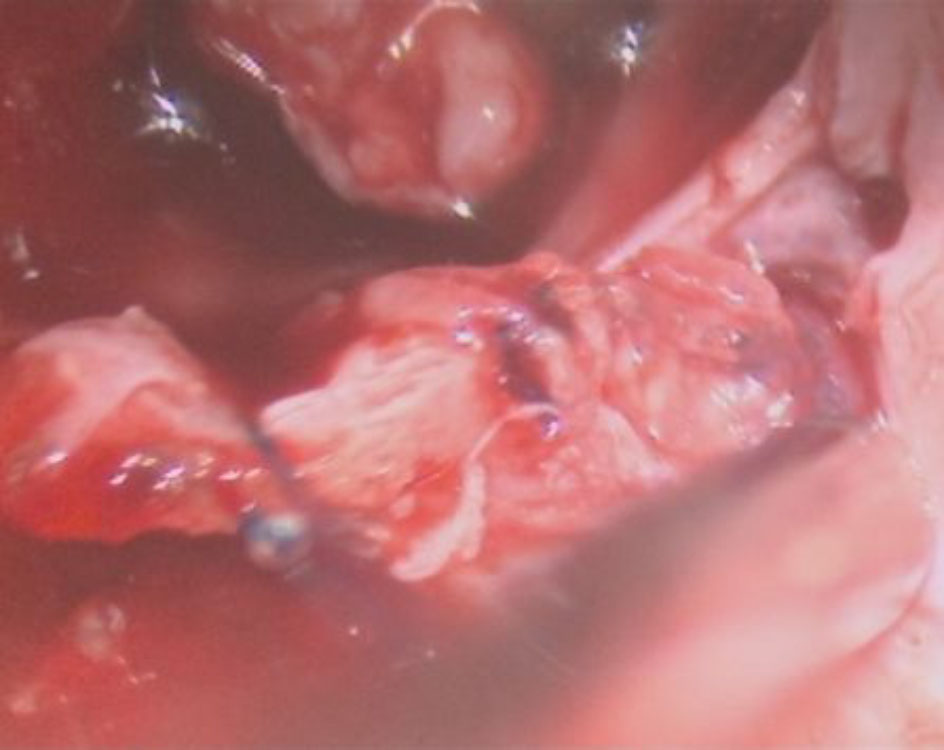

608

'25年2月

60代

右側頭葉腫瘤

頭蓋内腫瘍摘出術